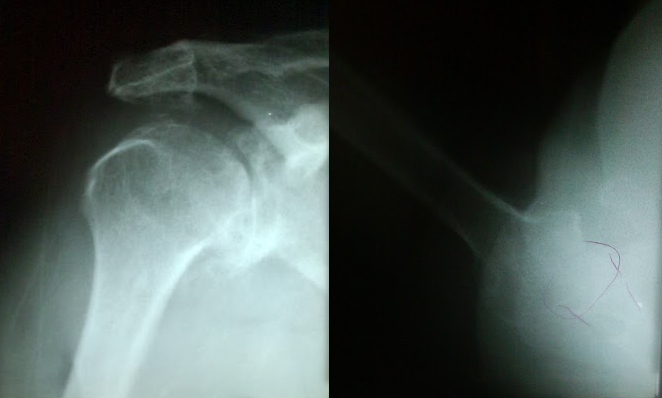

This is one of my first shoulder replacements, from 2010. 60-year old female with severe right shoulder arthritis, severe pain, stiffness, and grinding. On presentation, she was able to forward flex her shoulder only about 45 degrees, and with severe pain.

In the xrays below, note the irregular appearance of both the glenoid and humerus, the inferior ostephyte, and the degenerative cysts.